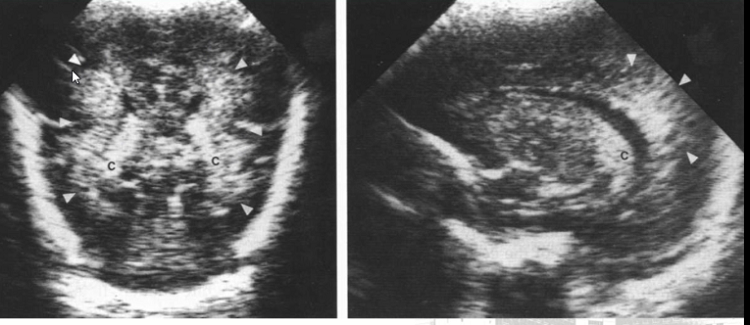

640 (1)

脑积水

640 (3)

颅内出血